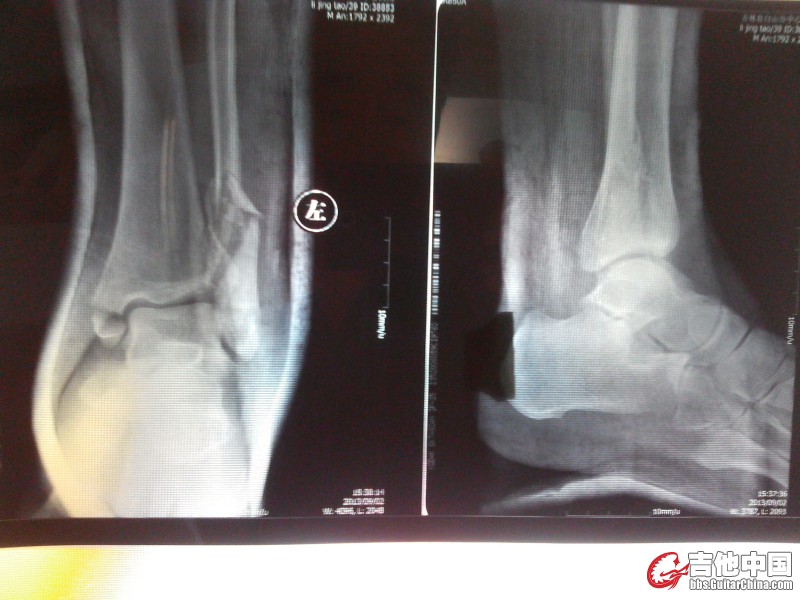

帮俺看看脚恢复得咋样

未手术

手术后

内踝、外踝的骨痂愈合不明显哦~

是啊 没见到骨痂

我猜是不是这新机器穿透性太强 应该找个老式X光机再查下

但是医生说骨折线已经模糊 肯定是在愈合

我现在走路没有不适感 只是不能负重

术后片子是你翻拍的时候没拍好 没有诊断意义,内踝那里感觉一根螺丝钉就搞定了